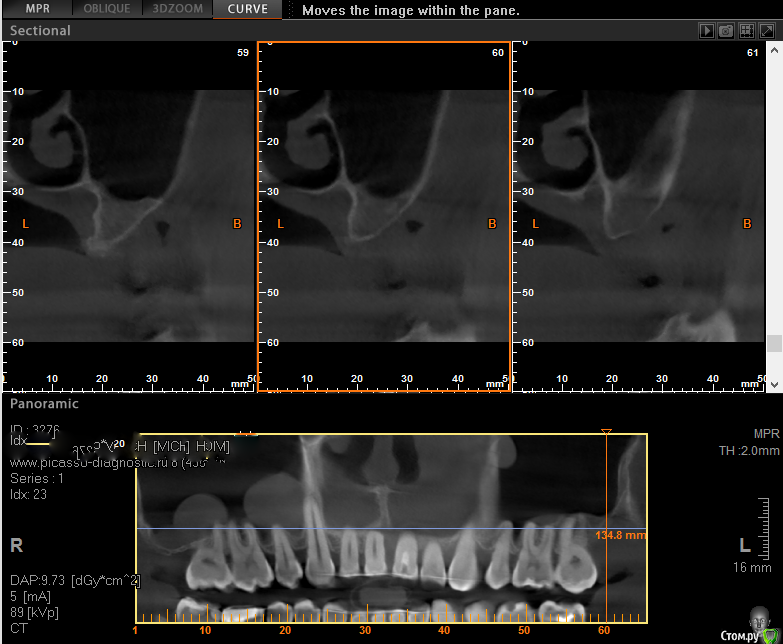

Тимур86 Опубликовано 11 августа, 2016 Поделиться Опубликовано 11 августа, 2016 вот такая ситуация...планировал удалить 12-22,через 3 месяца нкр и т.д....вопросы:1-стоит ли вообще 12 и 22 удалять?2-может нкр одномоментно с удалением?боюсь перегородки межзубные уйдути вообще-ваш план? Ссылка на комментарий

Yana guapa Опубликовано 12 августа, 2016 Поделиться Опубликовано 12 августа, 2016 это результат после ортодонтического лечения? Ссылка на комментарий

Тимур86 Опубликовано 12 августа, 2016 Автор Поделиться Опубликовано 12 августа, 2016 (изменено) это результат после ортодонтического лечения?да,при полном отсутствии работы с пародонтитом Изменено 12 августа, 2016 пользователем Тимур86 1 Ссылка на комментарий